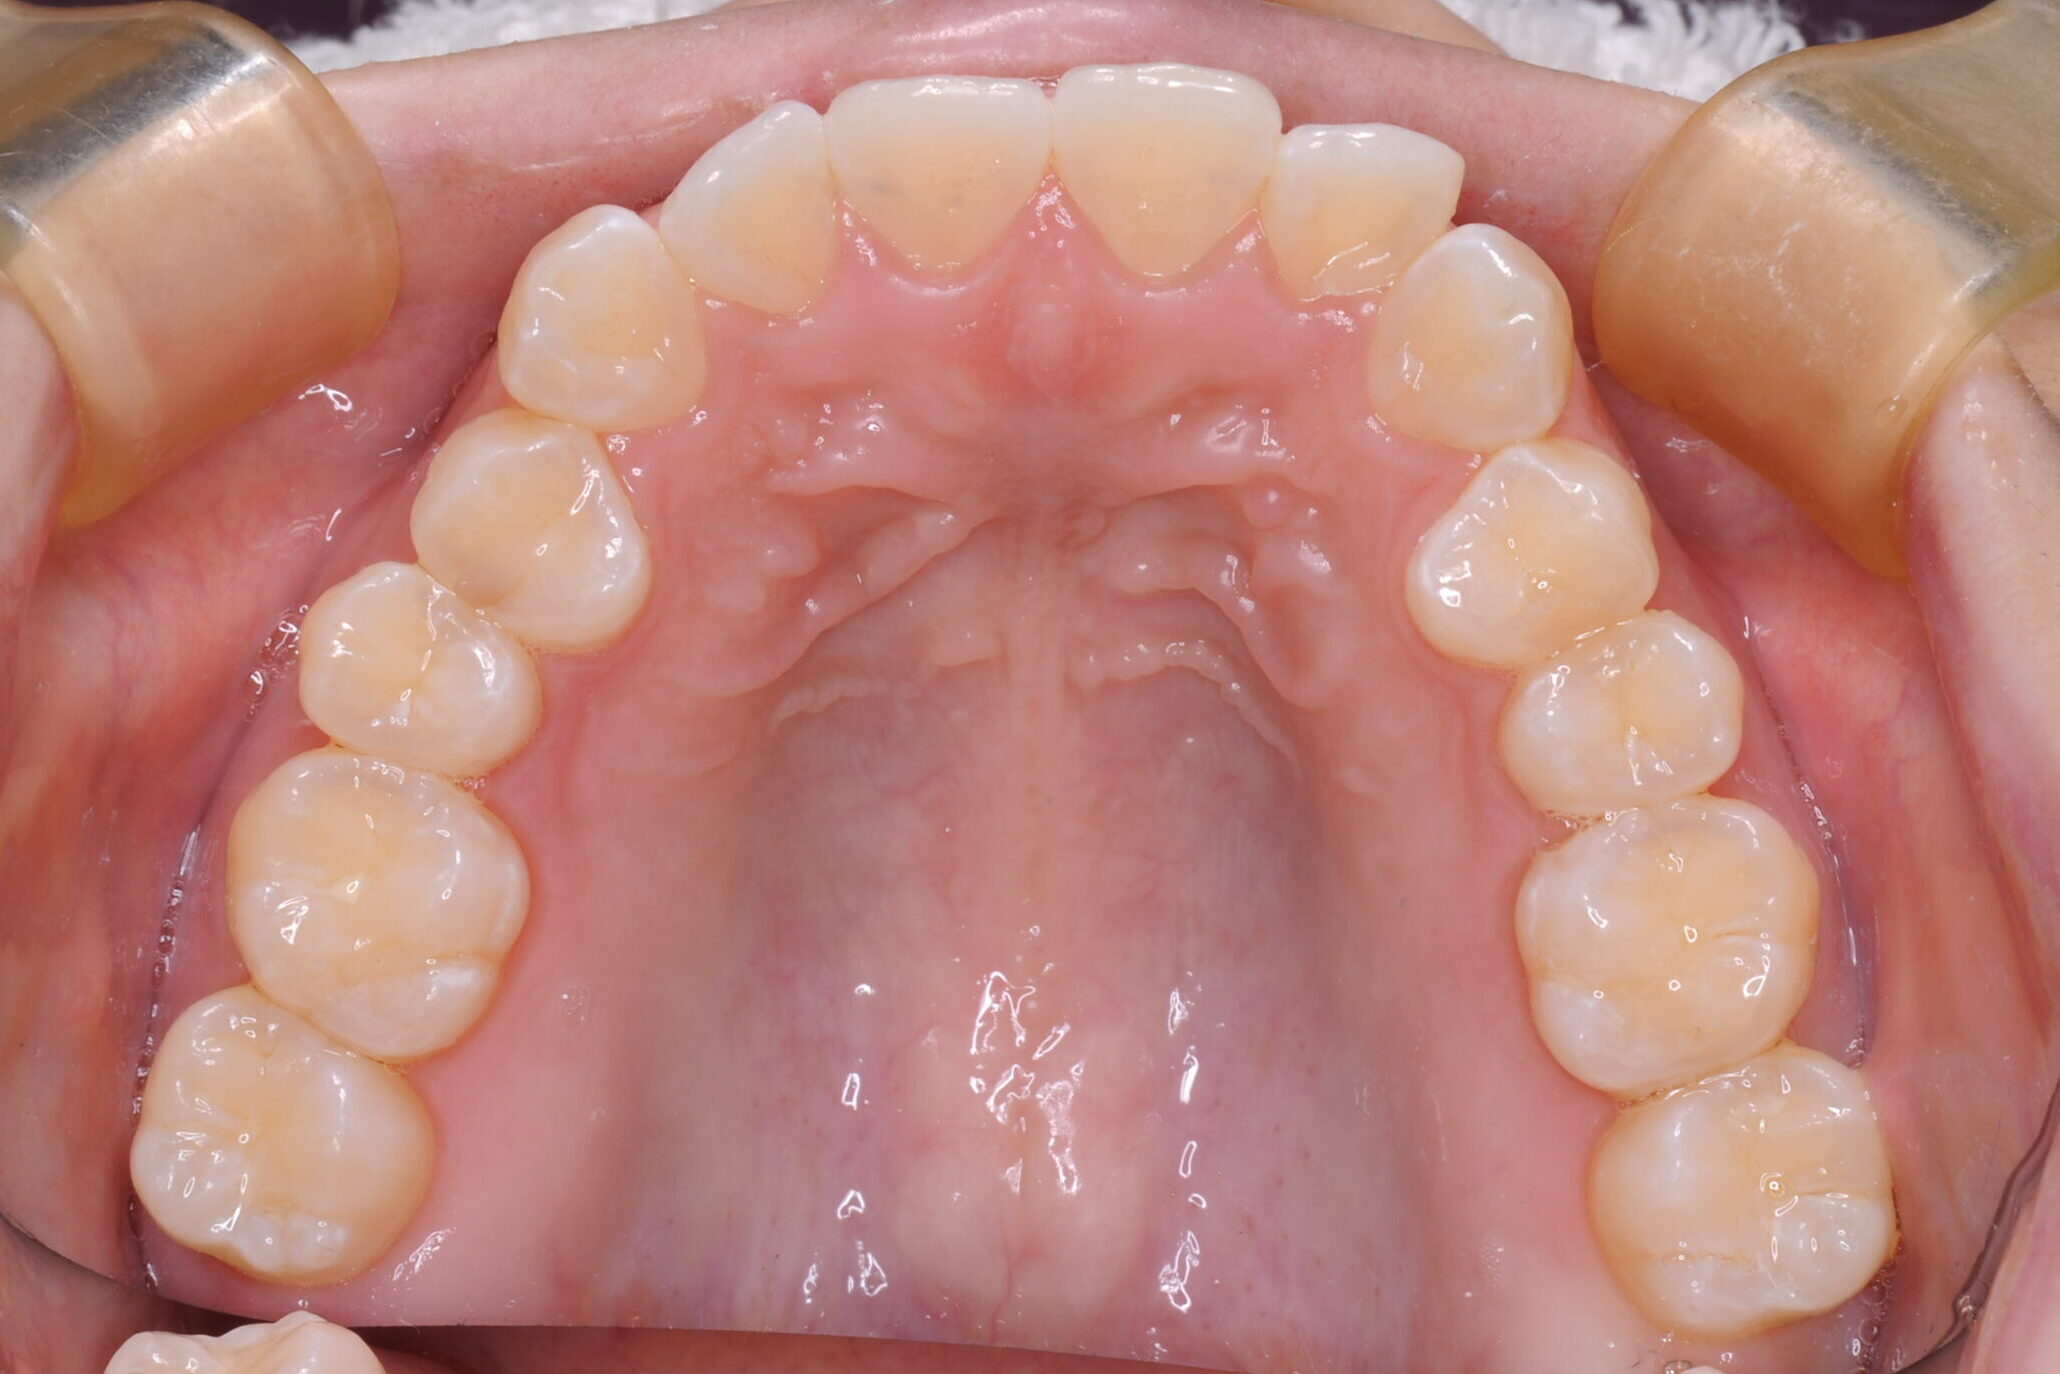

症例写真 before